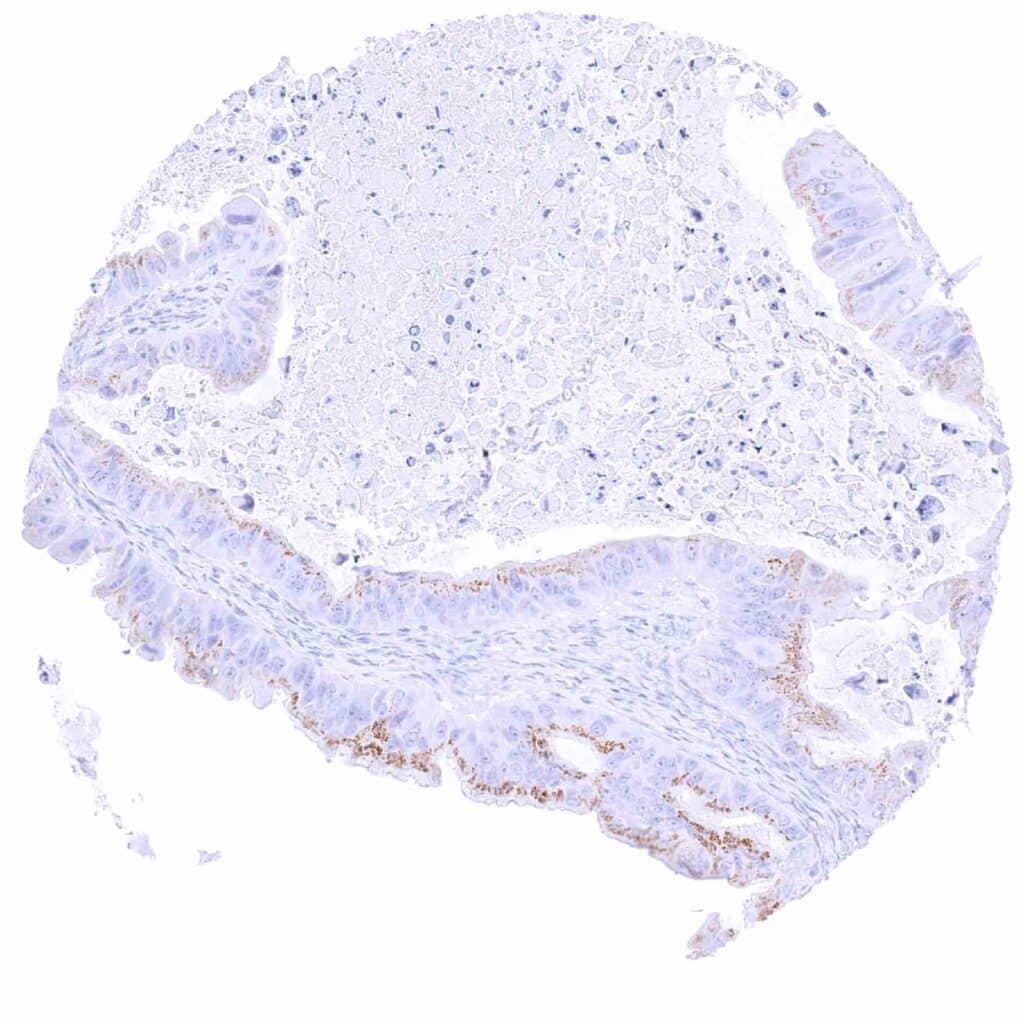

Pancreas – Ductal adenocarcinoma showing moderate granular perinuclear Prostein staining of neoplastic cells